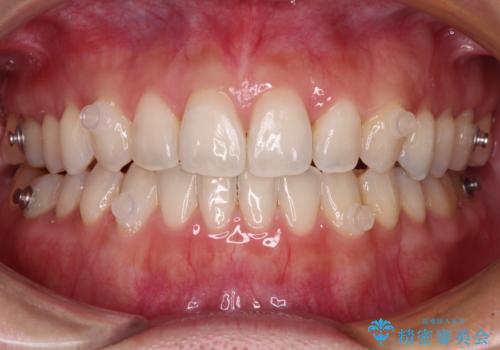

【モニター】狭い上顎歯列とオープンバイト 急速拡大装置を用いた矯正治療

- 前歯の開咬を気にして来院された患者様です。

上顎歯列が狭窄していたため、急速拡大装置により上顎骨を側方に拡大し、その後インビザラインにて矯正治療を行うこととしました。

舌の突出癖が開咬の原因であったので、改善のための舌トレーニングを行っていただきました。

舌トレーニングは後戻りにも大きく影響するため、とても重要なトレーニングです。